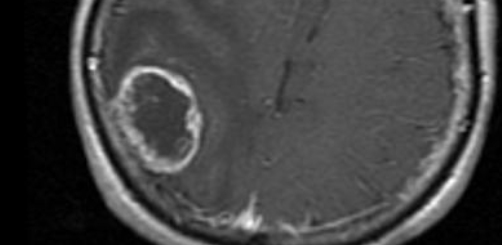

cerebrales cerebrale tumeur oligo dendro dendrogilome oligodendrogliome